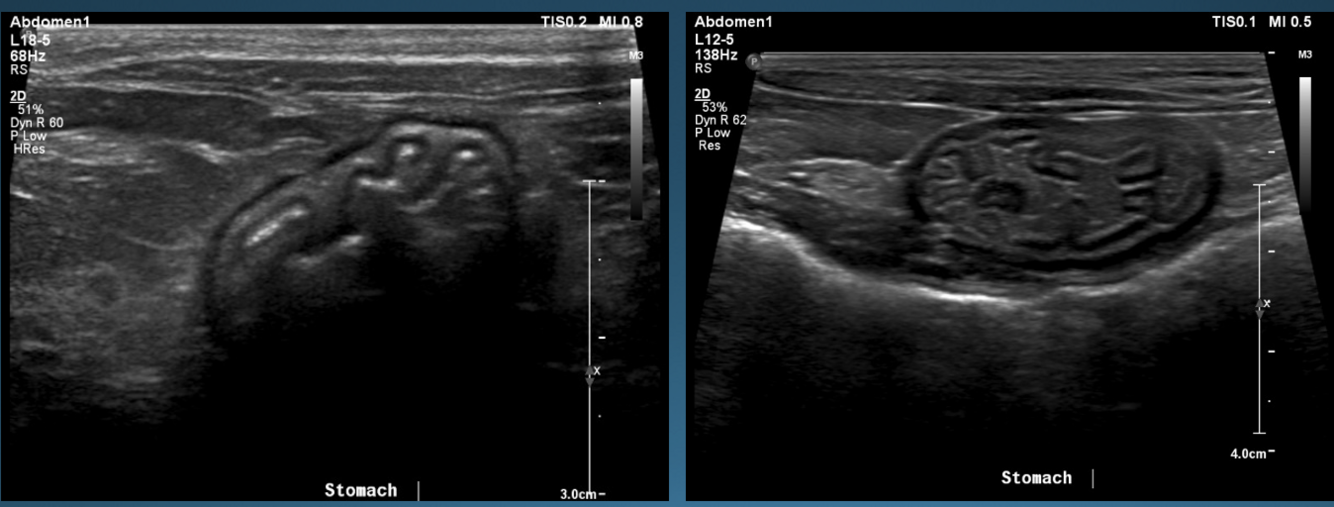

What is shown in these images?

A

normal stomach

-presence of rugal folds

-ability to assess gastric wall